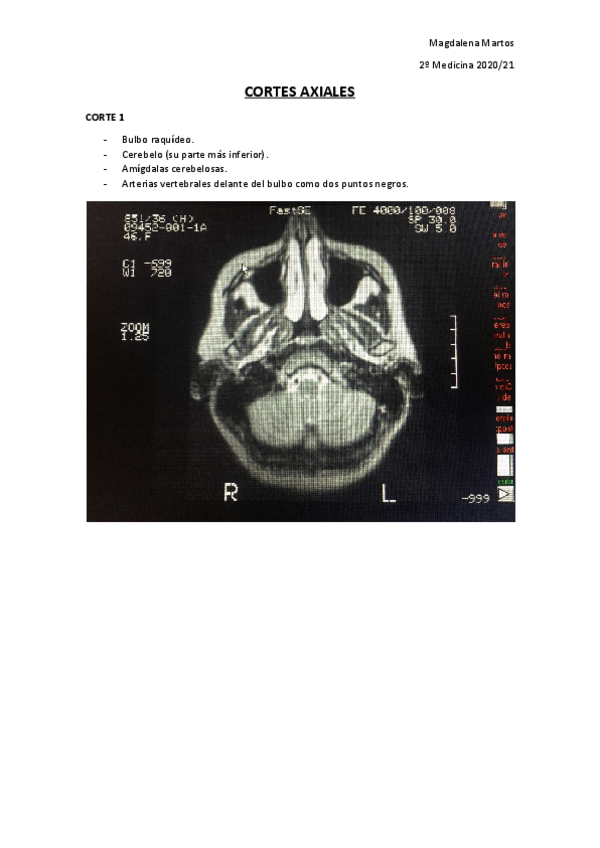

RESONANCIAS EXAMEN PRÁCTICO

He publicado nuevos apuntes de 2º Neurobiología: RESONANCIAS EXAMEN PRÁCTICO

Cortes-Axiales-Practico-Neuro.pdf